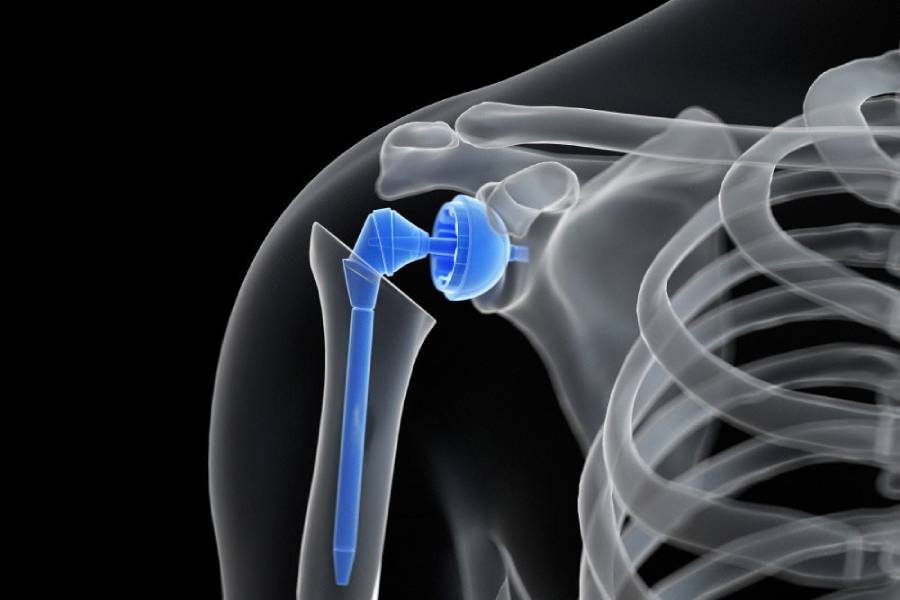

Joint Replacement Surgery, also known as Arthroplasty, is a medical procedure in which a damaged or worn-out joint is replaced with an artificial implant (prosthesis). These implants replicate the natural movement of a healthy joint, reducing pain and restoring mobility.

In simple terms, joint replacement means removing damaged cartilage and bone from a diseased joint and substituting it with a metal, plastic, or ceramic implant designed to function like a natural joint. It’s one of the most successful orthopaedic procedures today, improving millions of lives worldwide. Patients who undergo Total Joint Replacement Surgery typically regain strength, flexibility, and the ability to perform everyday activities without pain. You can also learn more about the joint replacement procedure through a joint replacement video demonstration, often shared during consultations at OrthoPatna, to help patients understand what to expect before and after surgery.

Though less common, replacement surgeries for the shoulder, elbow, and ankle are also performed for patients with severe joint damage or rheumatoid arthritis.